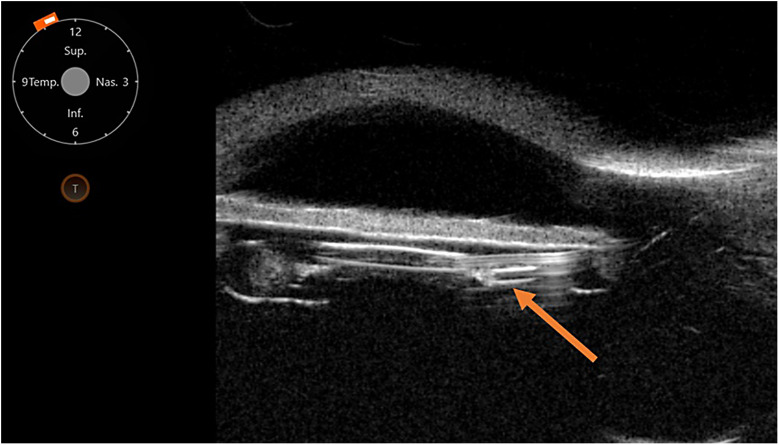

Case presentation: We describe a 64-year-old advanced pseudoexfoliation glaucoma patient who despite maximal tolerated medical therapy and two failed glaucoma surgeries, still suffered from uncontrolled intraocular pressure (IOP) of 36 mm Hg in his left eye. The patient underwent the implantation of the Preserflo MicroShunt. The shunt was placed nasally into an area of unscarred conjunctiva, with the anterior part of the shunt inserted into the ciliary sulcus. Postoperatively, the patient's IOP dropped to 6 mm Hg on the first day and stabilized at 11 mm Hg at the 6-month mark. An elevated, posteriorly located bleb was observed, and the patient no longer required additional topical medications. Endothelial cell (EC) count remained stable with no signs of corneal edema. The patient did not experience any serious postoperative complications.